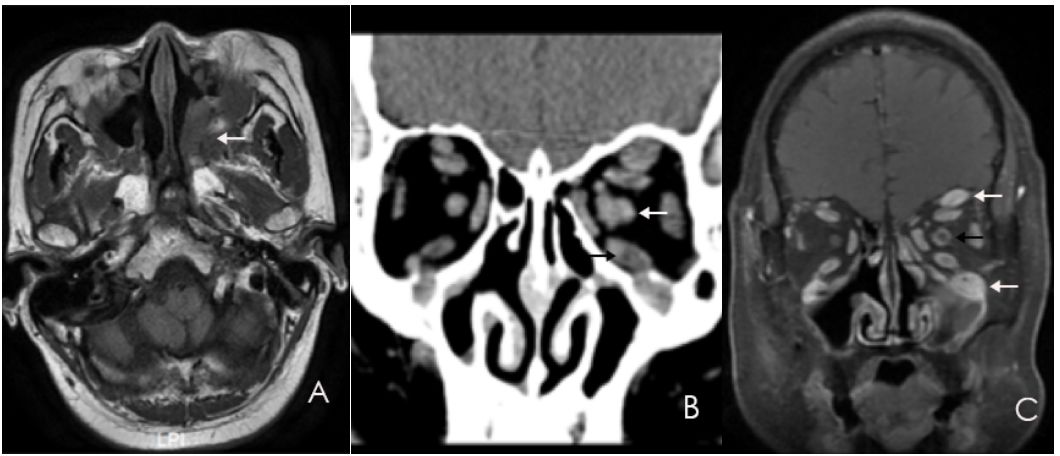

入院查体:双侧瞳孔等大等圆,对光反射灵敏,动眼自主,双眼视力轻度受损,双眼眶肿胀,左眼较重,左侧突眼。余颅神未见明显异常。辅助检查提示:免疫球蛋白G4:26.1g/L(0.03g/L~2.01g/),免疫球蛋白G:31.22g/L(7.00g/L~16.00g/L)。甲状腺功能均在正常范围,风湿免疫、血清肿瘤标志物结果均为阴性。影像学提示:眼外肌增粗,眶下裂增大,病变累及翼腭窝,三叉神经各分支明显增粗(图1A,B,C)。

图1. A:左侧眶下裂增大,病变累及翼腭窝(白剪头),局部软组织肿块。B:左侧眼外肌较右侧稍增粗(下黑剪头),左侧视神经增粗(上白剪头)。C: 左侧眶下神经(下白剪头)和额神经(上白剪头)明显增粗,左侧视神经鞘增厚且强化(黑剪头)。